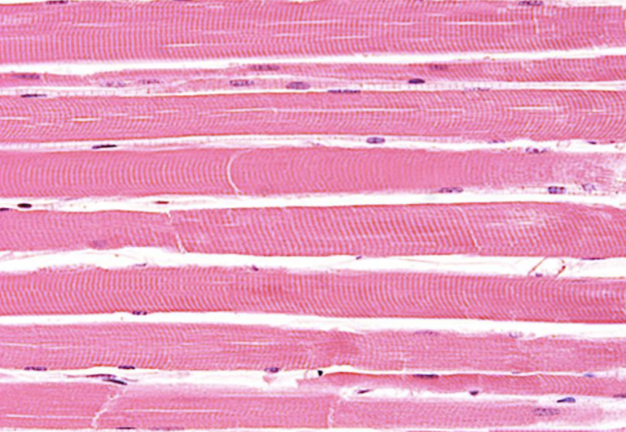

Indique tipo de tejido muscular

liso

Indique sitio anatómico donde se encuentra

organos

Indique característica propia

ausencia de estrias

Indique tipo de tejido muscular

esqueletico

Indique sitio anatómico donde se encuentra

inserto en el esqueleto

Indique característica propia

contracción voluntaria